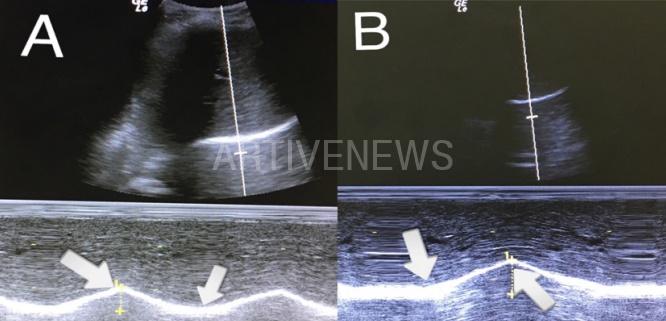

백석대 정성대 교수 논문에 따르면 여성 브라 속옷 실험 대상자는 충남 천안 소재의 B 학교 여대생 10명이었습니다. 이들은 실험실로 속옷을 입지 않고 들어와 20분간 침대에서 휴식을 취한 후 실험에 참가했다고 하는데요. 키, 몸무게, 가슴 사이즈 등을 측정한 후 브래지어 착용 전후의 흉곽 가동성, 가로막 움직임, 노력성 폐활량을 측정했습니다.

실험 참가 여학생 5명은 75A 사이즈였고, 나머지 5명은 85B 사이즈로 두 그룹으로 나뉘었습니다. 크기에 따라 어떤 실험 결과 차이가 있는지 확인하기 위함이었습니다. 흔히 크기가 클수록 속옷 착용시 문제가 더 많이 발생할 것이라는 '편견'이 있으나, 백석대 정성대 교수 논문을 통해 사실이 아님이 드러났는데요.

속옷을 입었을 때 사이즈에 상관없이 A그룹과 B그룹 여대생들 모두 흉곽 가동성과 가로막 움직임이 감소한 것으로 확인됐습니다. 특이한 점은 노력성 폐활량의 경우에는 75A 그룹에서만 감소한 것으로 확인됐습니다. 물론 전반적인 실험 결과, 두 그룹 간 유의한 차이는 발생하지 않은 것으로 확인됐습니다. 이에 정성대 교수 연구진은 "성인 여성 가슴 크기에 상관없이 브래지어 착용이 3가지 요소에 부정적 영향을 미칠 수 있다"고 결론냈습니다.